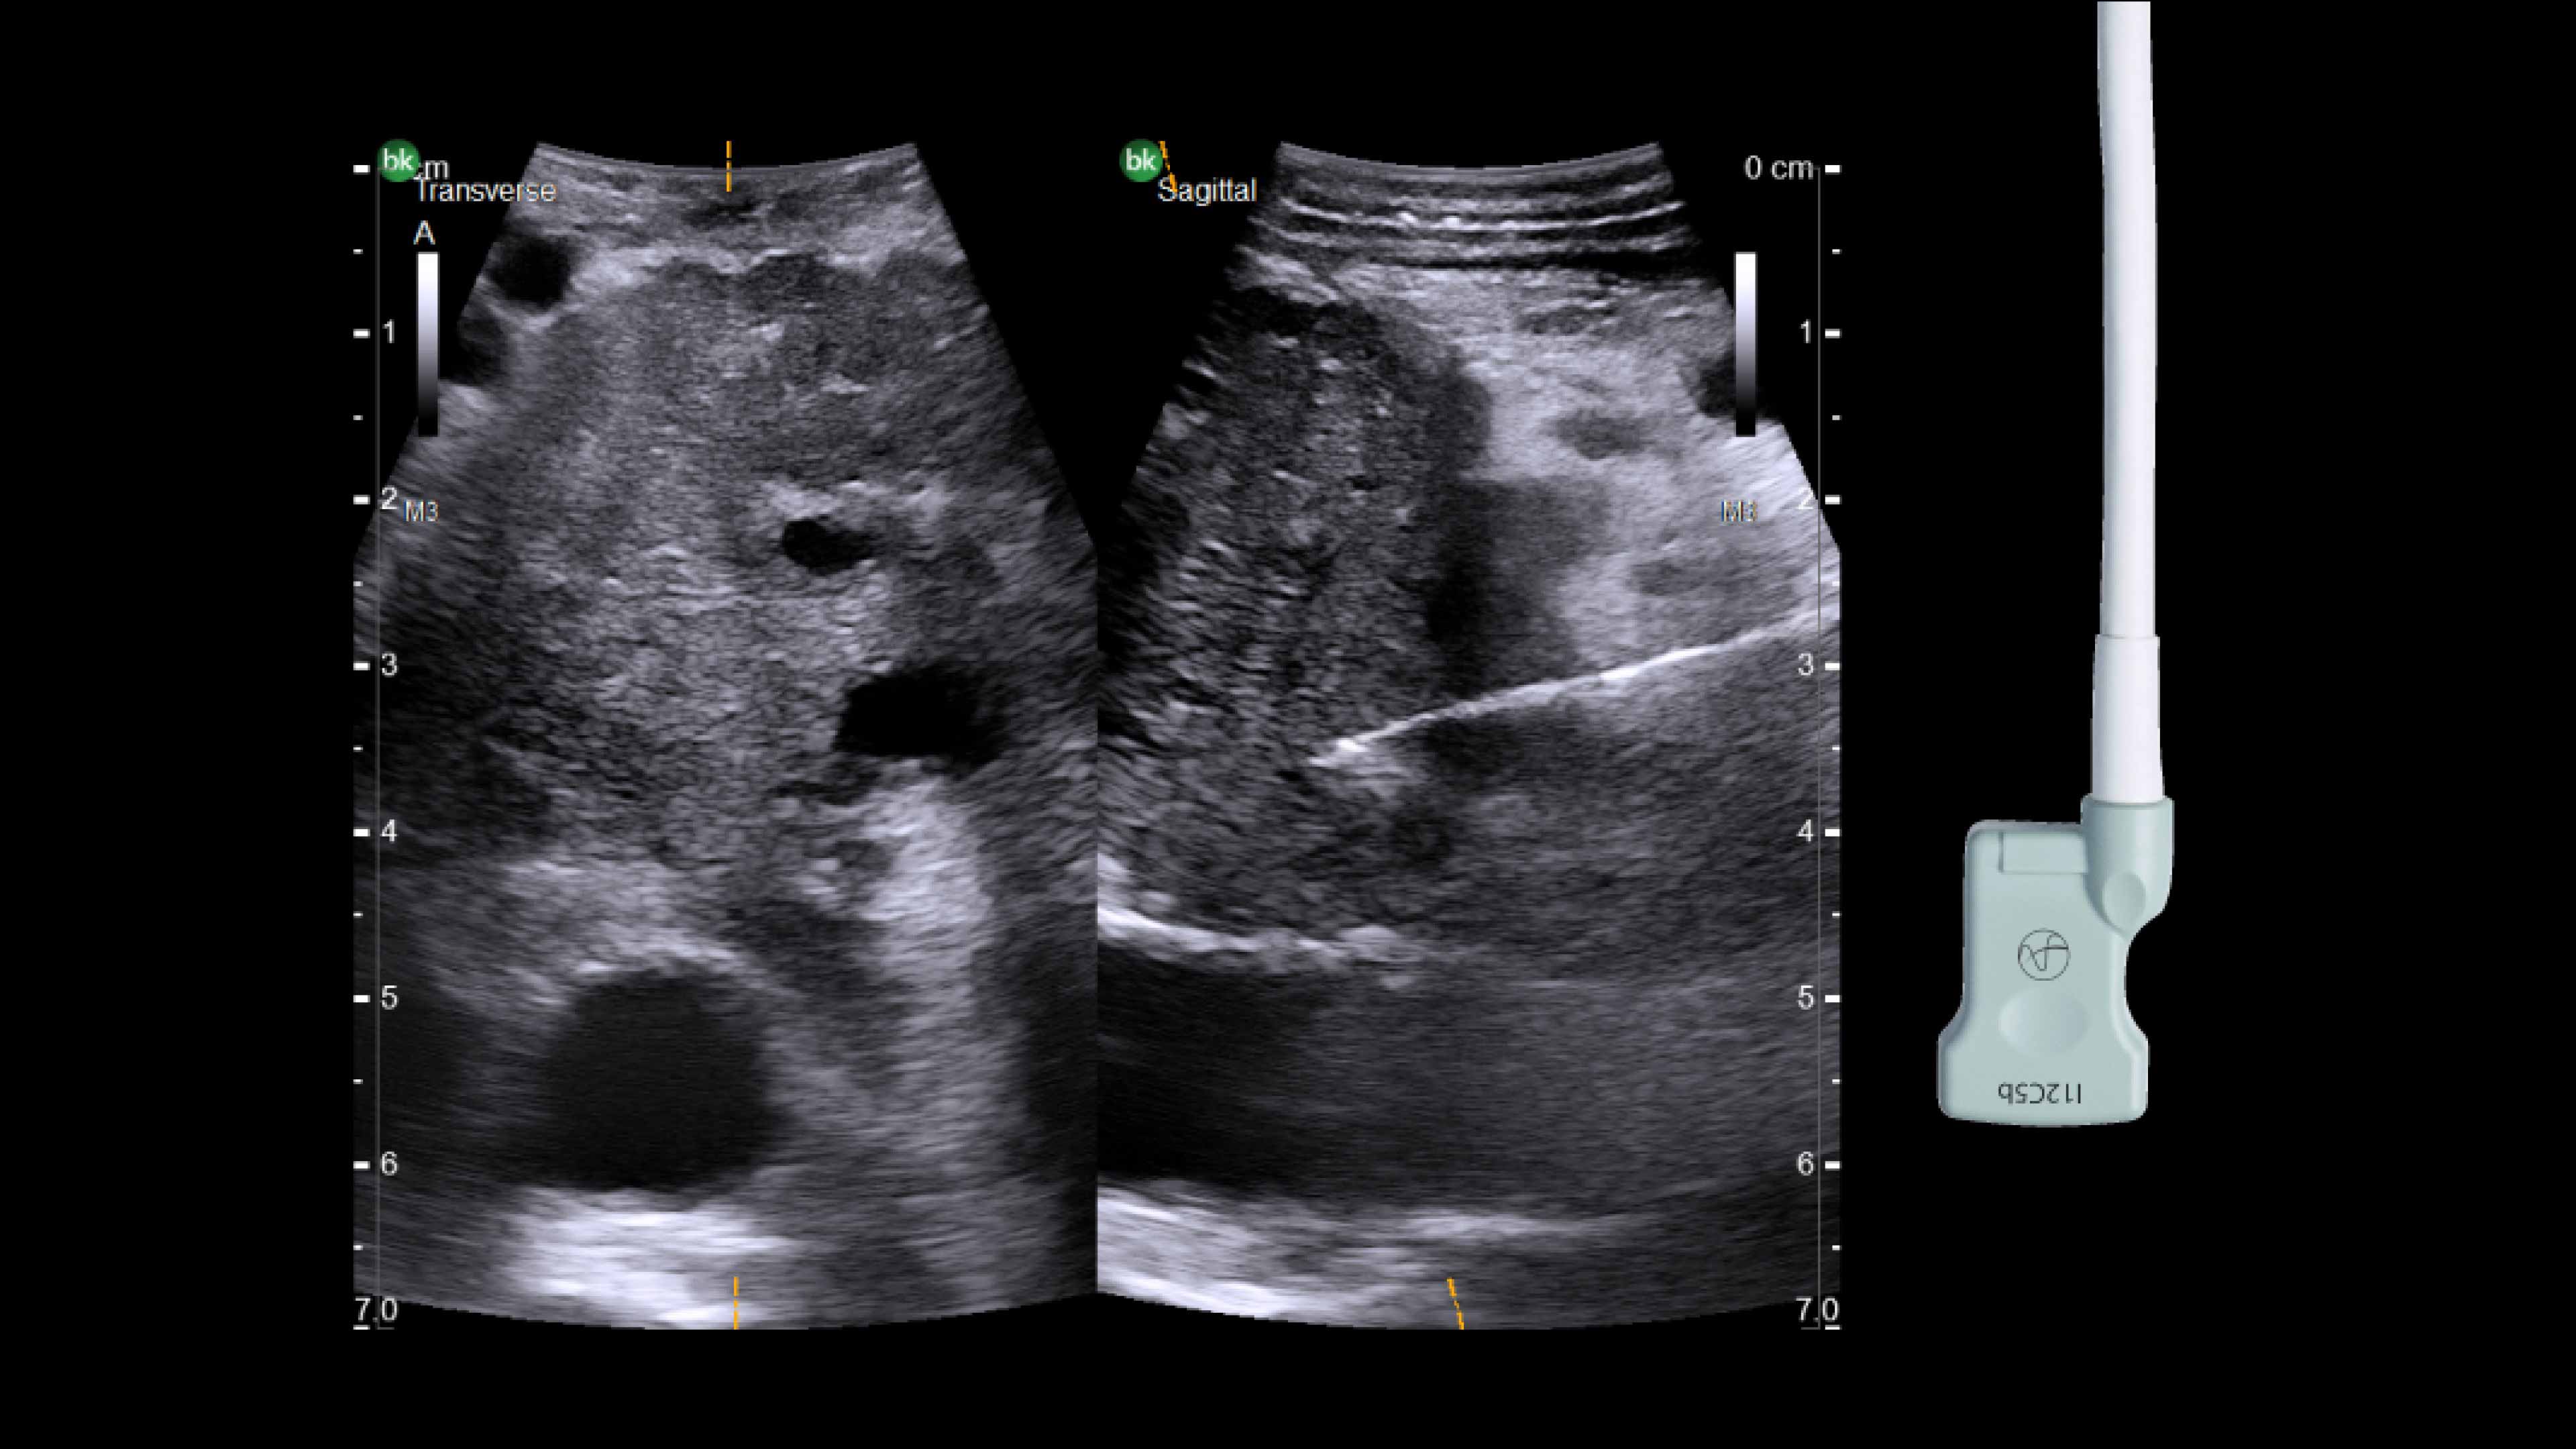

Active imaging supports liver and pancreas tumor resection procedures by helping you visualize complex anatomical variations and relationships to vascular structures, identify tumor location, define adequate margins of resection, and assess surgical planning.

Active imaging with intraoperative ultrasound supports critical decision-making in open or minimally invasive tumor resections.

• Visualize complex anatomical variations.

• Identify tumor location, proximity, and invasion of vasculature.

• Define adequate margins of resection.

• Understand relationship to vascular structures.

• Assess surgical planning and check for vessel patency at the end of the procedure.

Use of ultrasound during complex redo open liver resection.